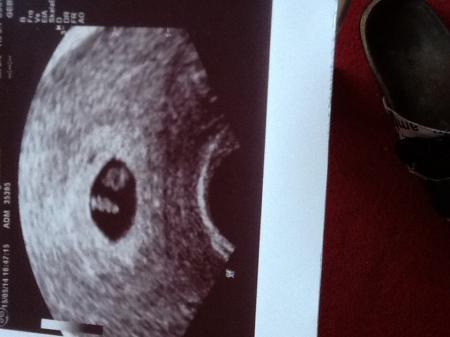

In der 6ssw fruchthöhle und 7ssw schon Fötus u dottersack. Hab mein Bild aus der 7ssw mir ran gehängt ;-) Liebste grüße

Bild zu